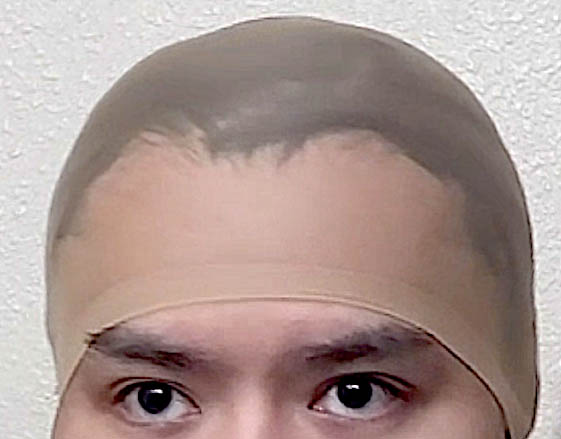

Patient 51

Desire for taller and rounder head shape.

Two stage custom skull implant augmentation technique.

Desire for taller and rounder head shape.

Two stage custom skull implant augmentation technique.